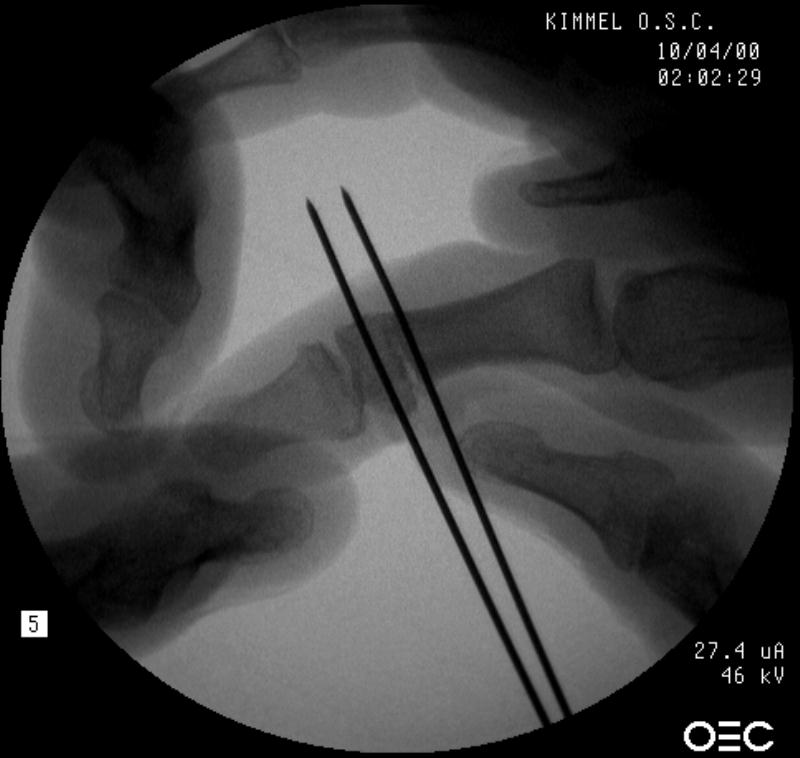

Osteotomy planning: proximal pin parallel to the proximal joint line, distal pin parallel to the distal joint line:

Click for larger image

Pins were used as saw blade alignment guides:

Osteotomy closed:

Intraosseous wire passed through pin tracts, interfragmentary pin: